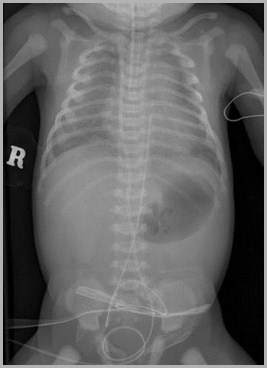

Umbilical venous catheter at junction between IVC and RAUmbilical artery catheter in distal aorta

Auckland